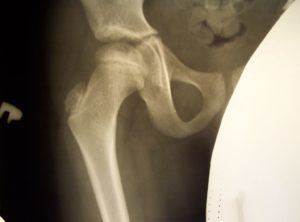

Рентгенографическое исследование тазобедренных суставов у детей, у которых заподозрена дисплазия Майера, позволило обнаружить более позднее по сравнению с нормой появление ядер оссификации. Наблюдается уменьшение в размерах либо недоразвитие хрящевой части эпифиза бедра.

Ядра окостенения появляются с запозданием, может появиться одно ядро и несколько сразу. В ряде случаев подобное приводит к ошибкам в диагностике, такое состояние расценивается, как очаги асептического некроза головки бедренной кости.

В конце прогрессирования дисплазии Майера возможно обнаружить на рентгеновском снимке сформировавшийся эпифиз бедренной кости с невыраженным уменьшением его размеров. Структура костной ткани и хрящевого покрытия при этом не имеет отклонений.

Рентгенограмма и ультразвуковое обследование отображают несовпадение центральной точки головки бедренной кости с центральной точкой в вертлужной впадине.